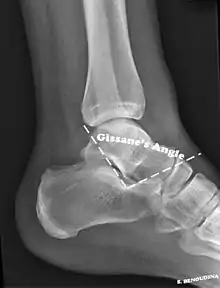

Conventional radiography is usually the initial assessment tool when a calcaneal fracture is suspected. Recommended x-ray views are (a) axial, (b) anteroposterior, (c) oblique and (d) views with dorsiflexion and internal rotation of the foot. However, conventional radiography is limited for visualization of calcaneal anatomy, especially at the subtalar joint. A CT scan is currently the imaging study of choice for evaluating calcaneal injury and has substituted conventional radiography in the classification of calcaneal fractures.[13] Axial and coronal views are obtained for proper visualization of the calcaneus, subtalar, calcaneocuboid and talonavicular joints.

The Angle of Gissane, or "Critical Angle", is the angle formed by the downward and upward slopes of the calcaneal superior surface. On a lateral radiograph, an angle of Gissane > 130° suggests fracture of the posterior subtalar joint surface. Böhler's angle, or the "Tuber Angle", is another normal anatomic landmark seen in lateral radiographs. It is formed by the intersection of 1) a line from the highest point of the posterior articular facet to the highest point of the posterior tuberosity, and 2) a line from the former to the highest point on the anterior articular facet. Böhler's angle is normally 25° to 40°.[14] It is named after Austrian physician Lorenz Böhler.[16] A decreased angle is indicative of a calcaneal fracture.